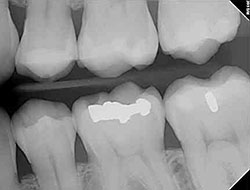

Digital X-Rays

Using the most advanced dental technology possible is just as important as staying up-to-date on the latest treatment techniques. Because our practice is dedicated to providing you with the safest and most convenient treatment options available, we utilize advanced digital X-ray technology in our office.

Digital X-rays provide several advanced imaging options that are designed to save time, provide clearer dental photos, and expose patients to less radiation than with traditional X-ray technology.